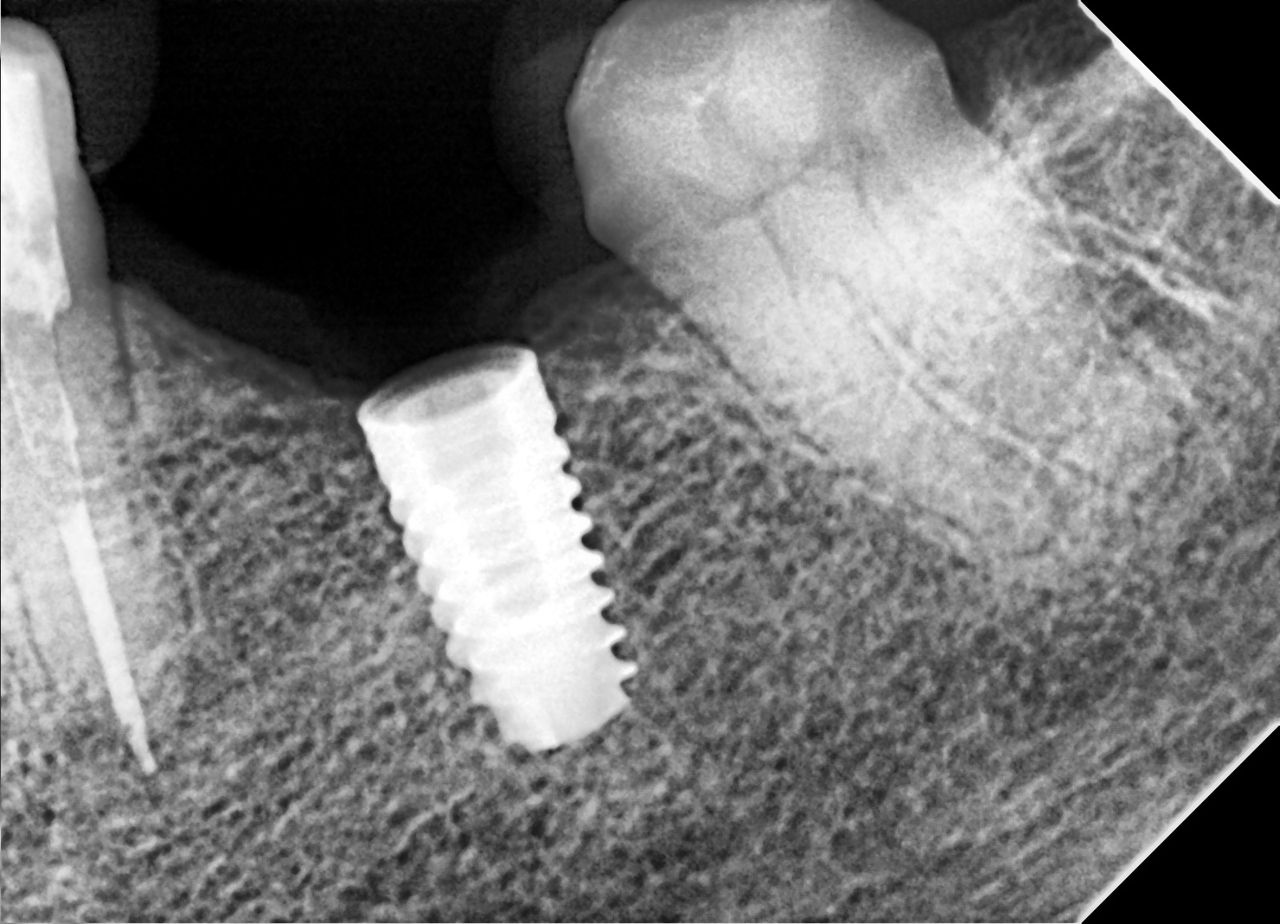

Colocación de implantes con tecnología avanzada

Hoy realizamos la colocación de dos implantes dentales, un procedimiento planificado y ejecutado con guía quirúrgica de implantes, lo que nos permite obtener una colocación más exacta, segura y predecible